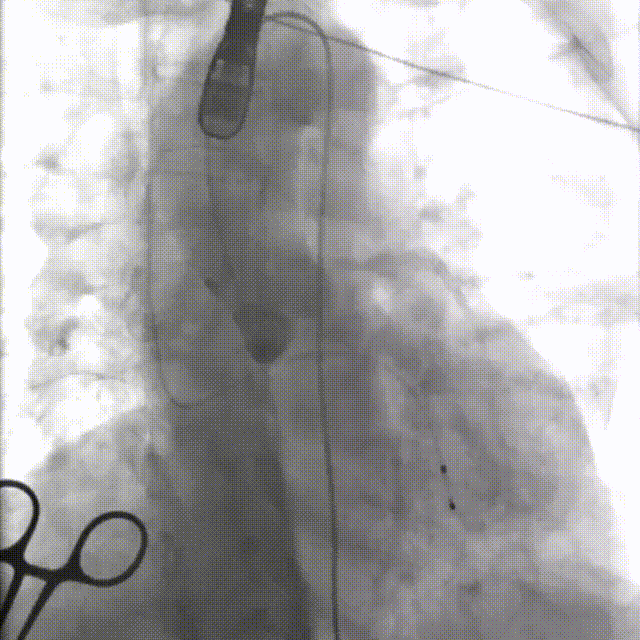

输送器过弓

瓣下3mm定位

左冠窦侧偏深,需回收再定位

回收调整至零位定位,释放到工作位位置合适